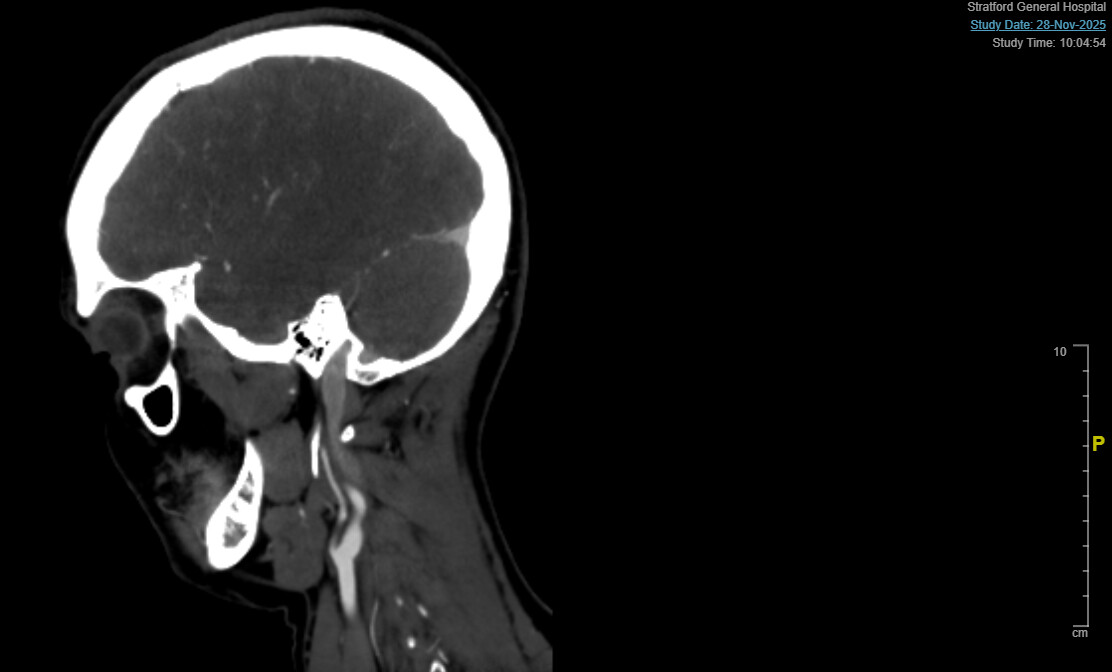

@Isaiah_40_31 @Jules @TML I had my CTA - they had to use a different dye due to my allergy to the IPV type they usually use. I’d love to have some thoughts on some of the images.

I’m not able to label the scans, but looking at the first two images there looks to be some compression between the styloid (or calcified stylo-hyoid ligament; there seems to be a gap, so not sure if that’s the CT not catching it) and the C1 process.

On the 4th image, it looks like your hyoid bone processes are pretty long, & seem to be close to, or touching your carotid arteries (I’m sorry I’m not knowledgeable enough to say for sure).

Yes, sorry, it looks like the IJV is compressed between the styloid/ calcified ligament & the C1 process.

I’ve annotated 3 of your images though I’m not sure which of the 2 profile pictures is your left side & which is your right so I didn’t label left/right on the images. The third image is the one w/ your hyoid bone & I’m fairly certain what I marked as the internal carotids is correct but I’m not positive so I put ? after each one. If those are your internal (or external) carotids then at the very least the greater horns of your hyoid are poking them. At the worst, they’re causing compression w/ the left looking worse than the right side.

@Isaiah_40_31 wow amazing thank you so much!!! Would there be another image that would be helpful….there are so many I don’t really know what to send. Ty!!! Chatgpt says 85 percent compression of ijv at certain points